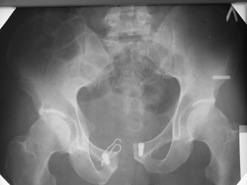

Диагноз : Сочетанная травма. ЗЧМТ. Перелом свода черепа. Ушиб головного мозга.Разрыв лонного и крестцово-подвздошного сочленений с нарушением целостности тазового кольца, с массивной забрюшинной гематомой и пропотеванием в брюшную полость. Перелом 10 ребра справа, осложненный гемопневмотораксом справа, правосторонней пневмонией на фоне ушиба правого легкого. Шок 3-4 ст. Больной поступил в отделение 07.03.2005г. в 16.00 в экстренном порядке через 30 минут после автодорожной травмы.Доставлен КСП. При поступлении состояние больного крайне тяжелое, явления травматического шока, А/Д-80/60 мм.рт. ст. ЧСС-120.В экстренном порядке поднят в операционную, интубирован, совместно с диагностическими мероприятиями лечение шока.При осмотре выявлены перелом 10 ребра справа, разрыв лонного и правого крестцово-подвздошного сочленений. Имеется линейный перелом теменной и височной костей слева с переходом на основание. Диагностическая лапароскопия 07.03.2005г. в 16.30-массивная забрюшинная гематома малого таза.Оставлена контрольная, дренажная трубка.Учитывая кровь в моче произведена цистография - данных за разрыв мочевого пузыря не найдено. Больной переведен в реанимационное отделение.За 08.03.2005г. из брюшной полости выделилось до 1500,0 мл, крови, часть крови реинфузирована. 08.03. в 06.30 наложен торокоцентез справа,удалено 100,0 мл. крови и 200,0 мл. воздуха .. Учитывая продолжающеееся кровотечение в брюшную полость из перелома костей таза, для исключения возможного разрыва внутренних органов 09.03.2005г. произведена Видеолапароскопия., на которой повреждения органов брюшной полости не выявлено.Одновременно произведен шов лонного сочленения проволокой и винтами, с одномоментным наложением стержневого аппарата на кости таза, с целью уменьшения кровотечения из разрывов тазовых сочленений, дренирование гематом. В последующем состояние больного оставалось тяжелым. 10.03.наложена нижняя трахеостома.Далее неоднократно производилась лечебно-диагностическая ФБС.С 10.03 выявлена правосторонняя плевропневмония. КТ головного мозга от 10.03-субарахноидальноекровоизлияние.Срединные структуры не смещены. КТ-контроль от 15.03-открытая моновентрикулярная гидроцефалия4 желудочка. Полисинусит. Постепенно состояние больного медленно прогрессировало к улучшению.С 24.03 переведен на самостоятельное дыхание, а 09.03 переведен в травматологическое отделение.Аппарат стержневой снят из-за перелома стержня (раскрутил больной самостоятельно).После госпитализации в наше отделение проведено дополнительное обследование Рентгекнография, КТ.Хотелось бы услышать Ваше мнение о дальнейшей тактике.-- С уважением, Leonid

Углядел билатеральное повреждение таза. Имеется вертикальная нестабильность со стороны перелома боковой массы крестца, ротационная с контрлатеральной стороны - чрезподвздошный разрыв кп сочленения. Разрыв лона, запирательные отверстия вроде целы.

DS. на сегодняшний день: Вертикальная двусторонняя нестабильная деформация таза, неправильно срастающийся перелом боковой массы крестца слева, срастающийся перелом крыла правой подвздошной кости, застарелый частичный разрыв правого кп сочленения, застарелый разрыв лонного сочленения.